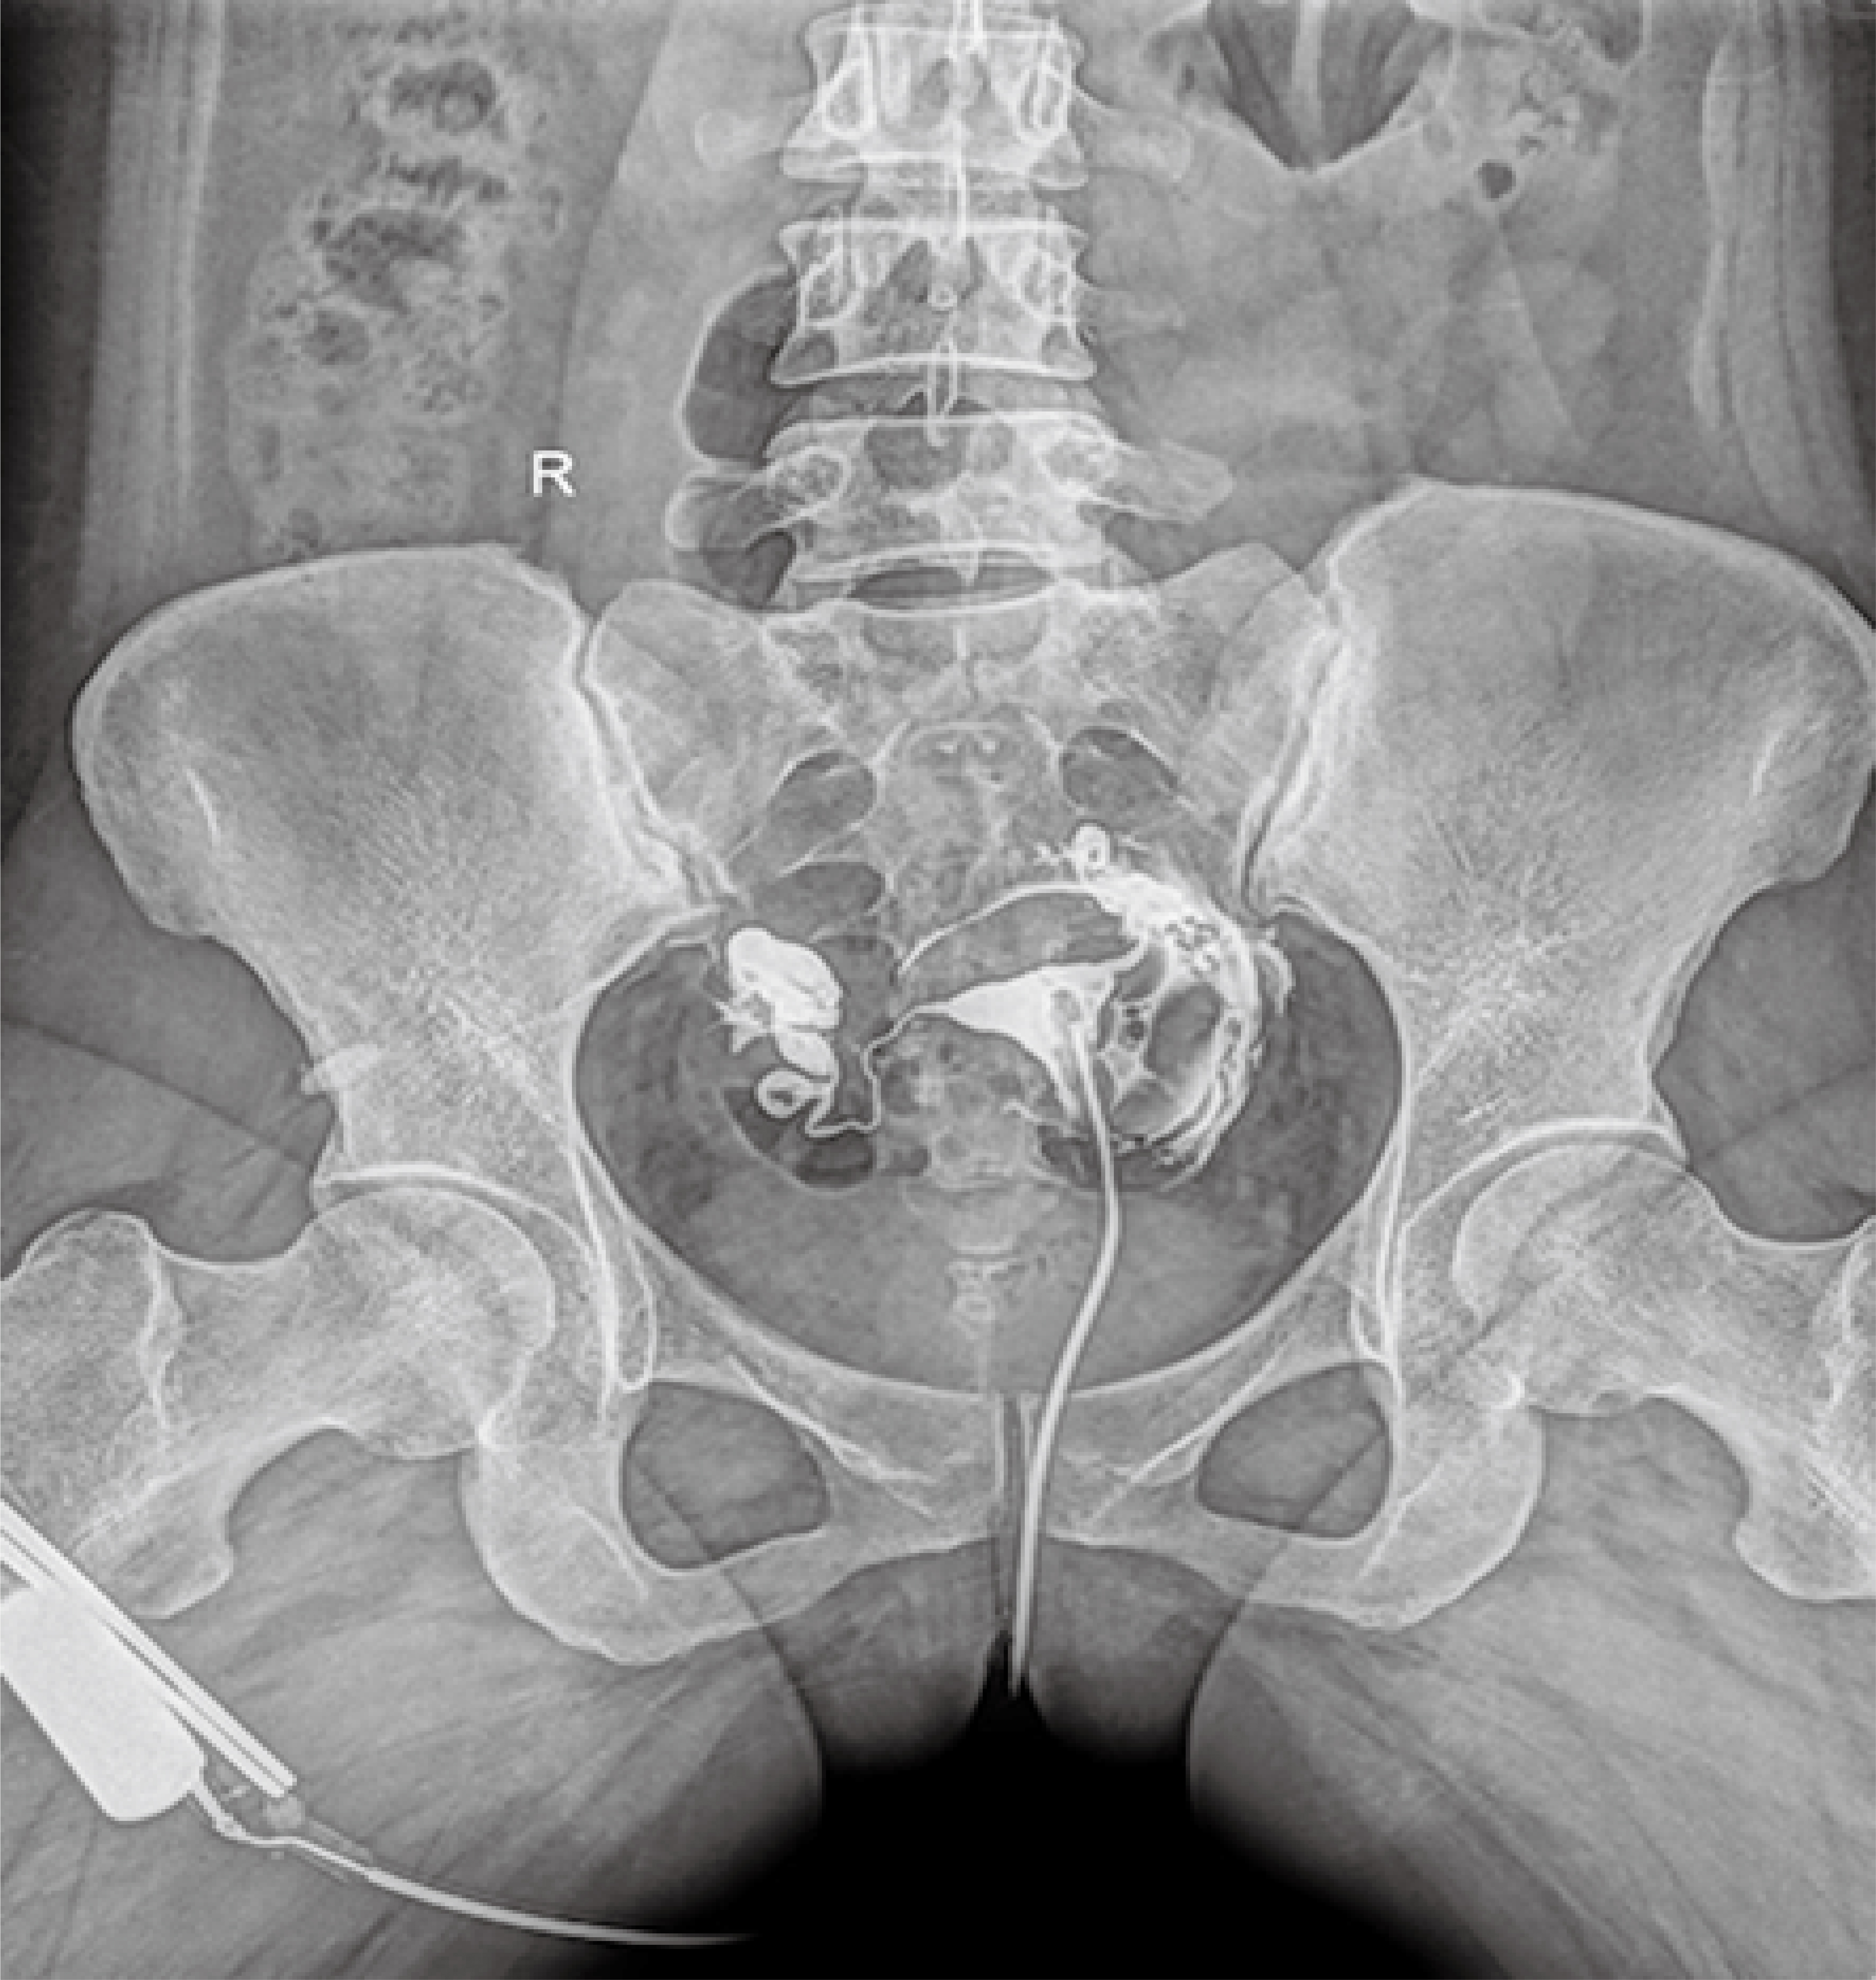

普利德醫(yī)療自主研發(fā)的新一代數(shù)字化X線透視攝影系統(tǒng),可應(yīng)用于DR攝影、數(shù)字透視、數(shù)字造影以及可視化精準DR拍片等多種臨床X線檢查領(lǐng)域。

● 17*17英寸的超高清像素動態(tài)平板探測器,更大的視野范圍,無需移動即可觀察整個動態(tài)過程,避免拖尾、噪聲對圖像的影響;

● 高效動態(tài)平板技術(shù),圖像不會有幾何畸變,提供高分辨率和精確的圖像,為醫(yī)生臨床診斷提供精準依據(jù);

● 最高幀速可達30幀/秒,動態(tài)采集清晰流暢,避免漏診、誤診情況的發(fā)生;

● 在可視過程或回放過程中,如發(fā)現(xiàn)疑似病灶,可進行毫秒級高清點片,隨時抓取單幀圖像,精準捕抓病灶。